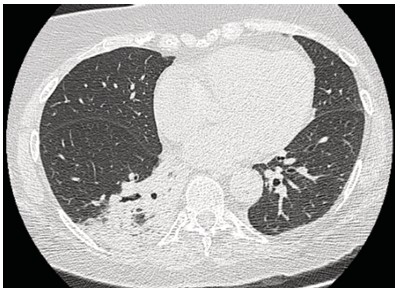

Mujer de 73 años procedente de Australia con antecedentes de hipertensión arterial, depresión, tiroiditis de Hashimoto e hipotiroidismo secundario. En las últimas semanas, como parte de su recorrido por Sudamérica, visitó Chile, Brasil, Argentina y Perú. En este último y durante su estancia en Machu Picchu, debuta con un cuadro clínico caracterizado por astenia, disnea de moderados esfuerzos, tos seca y cefalea opresiva holocraneana, tratada con medicación no especificada con mejoría parcial. Sin embargo, pocos días después y tras su llegada a Ecuador los síntomas se agudizan con aumento de la frecuencia e intensidad de la tos, así como la disnea y el compromiso general caracterizado por astenia, alza térmica y escalofrio. Tras esta presentación clínica es ingresada en el servicio de Emergencia destacando en la valoración clínica taquipnea (24 respiraciones por minuto), hipoxemia medida por pulsioximetría en 79%, con necesidad de aporte de oxígeno suplementario, taquicardia (100 latidos por minuto). En la auscultación pulmonar con presencia de crepitantes difusos y sibilancias basales, además edema de miembros inferiores. Dentro de la evaluación complementaria destaca la presencia de leucocitosis y neutrofilia, elevación de proteína C reactiva y la elevación significativa del dímero D (tabla 1). El panel respiratorio por PCR de 13 patógenos fue negativo. En los estudios de imagen infiltrados alveolares multilobares con broncograma aéreo y un estudio angiotomografico sin evidencia de defectos de llenado que sugieran tromboembolia pulmonar (TEP) (figuras 1-3).

Figura 3. Tomografía de tórax de alta resolución, corte axial. Izquierda: presencia de consolidado en lóbulo inferior derecho. Derecha: Língula.